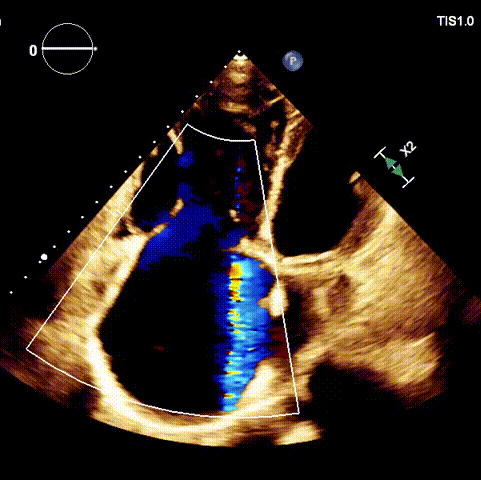

術前超聲

術后超聲